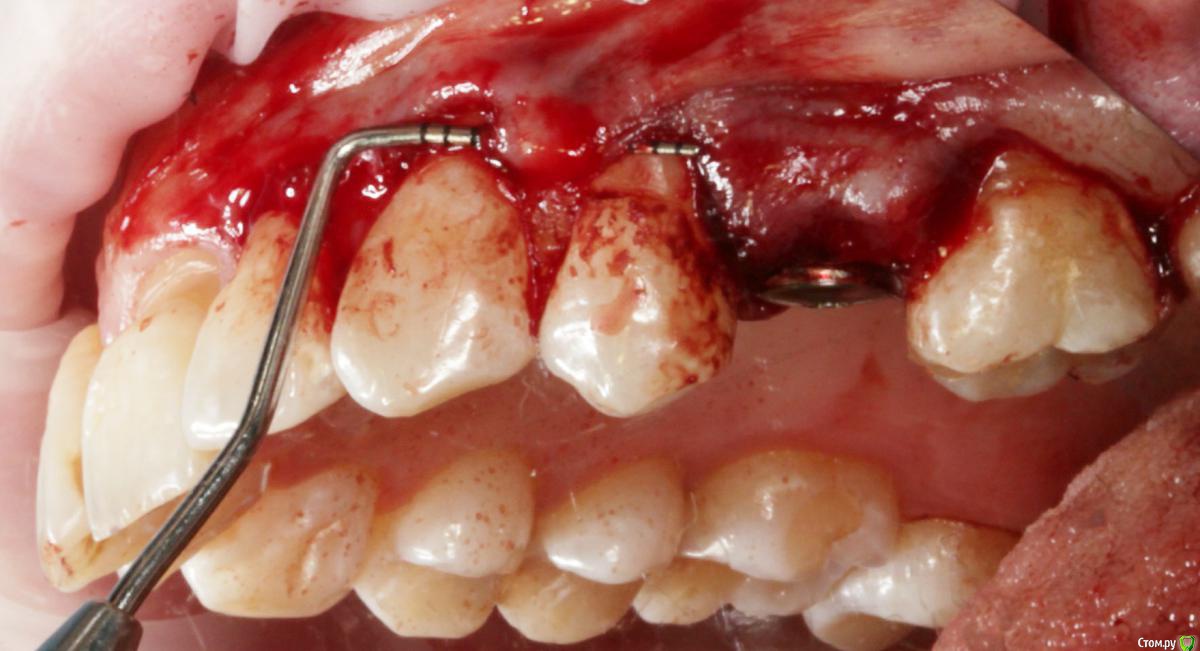

Dmitry DK Опубликовано 31 августа, 2019 Поделиться Опубликовано 31 августа, 2019 Доброго дня! Первичное обращение пациентки было связано с отсутствием 25 зуба, эстетические нарушения слизистой, клиновидные деф-ты в области других зубов - не смущали.В итоге решили, раз проводим операцию ( импл + ССТ ), закроем попутно и рец на верхней челюсти.Реставрацию на 21 зуб все не ставит... Приятных тебе выходных! ) Пациентка проходила лечение 2,5 года назад, пришла на проф осмотр 7 Ссылка на комментарий

Dman Опубликовано 2 сентября, 2019 Поделиться Опубликовано 2 сентября, 2019 ничего себе попутно, в итоге на имплант 15 минут, а на рецессии 2 часа?)) Ссылка на комментарий

Dmitry DK Опубликовано 2 сентября, 2019 Автор Поделиться Опубликовано 2 сентября, 2019 ничего себе попутно, в итоге на имплант 15 минут, а на рецессии 2 часа?))У меня те же мысли были), но согласитесь, что если бы мы этого не сделали - разница в зенитах былабы слишком велика Ссылка на комментарий